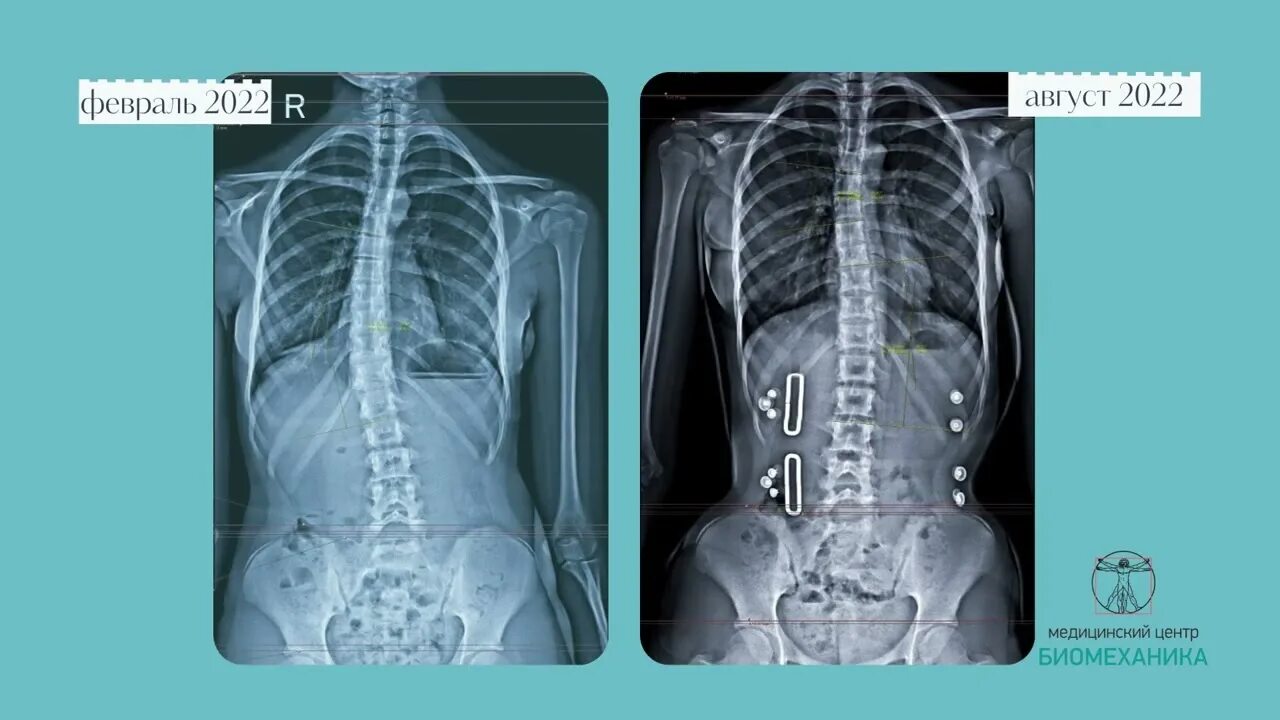

Сколиоз 2ст